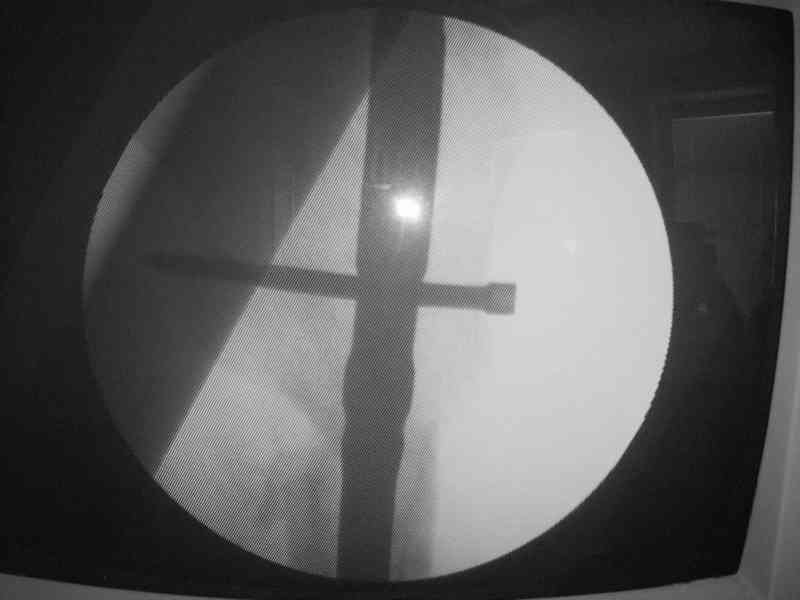

К сожалению под рукой только одна картинка от этой операции.

Я пошел на операцию имея стерильным и обычный бедренный гвоздь ChM и реконструктивный.

Когда открыто убрали DHS встали перед выбором, что ставить? Так, как это был подвертельный перелом - поперечная линия на уровне малого вертела то поставили обычный бедренный гвозь и один прокс блокирующий винт, который затянули компрессирующей заглушкой.